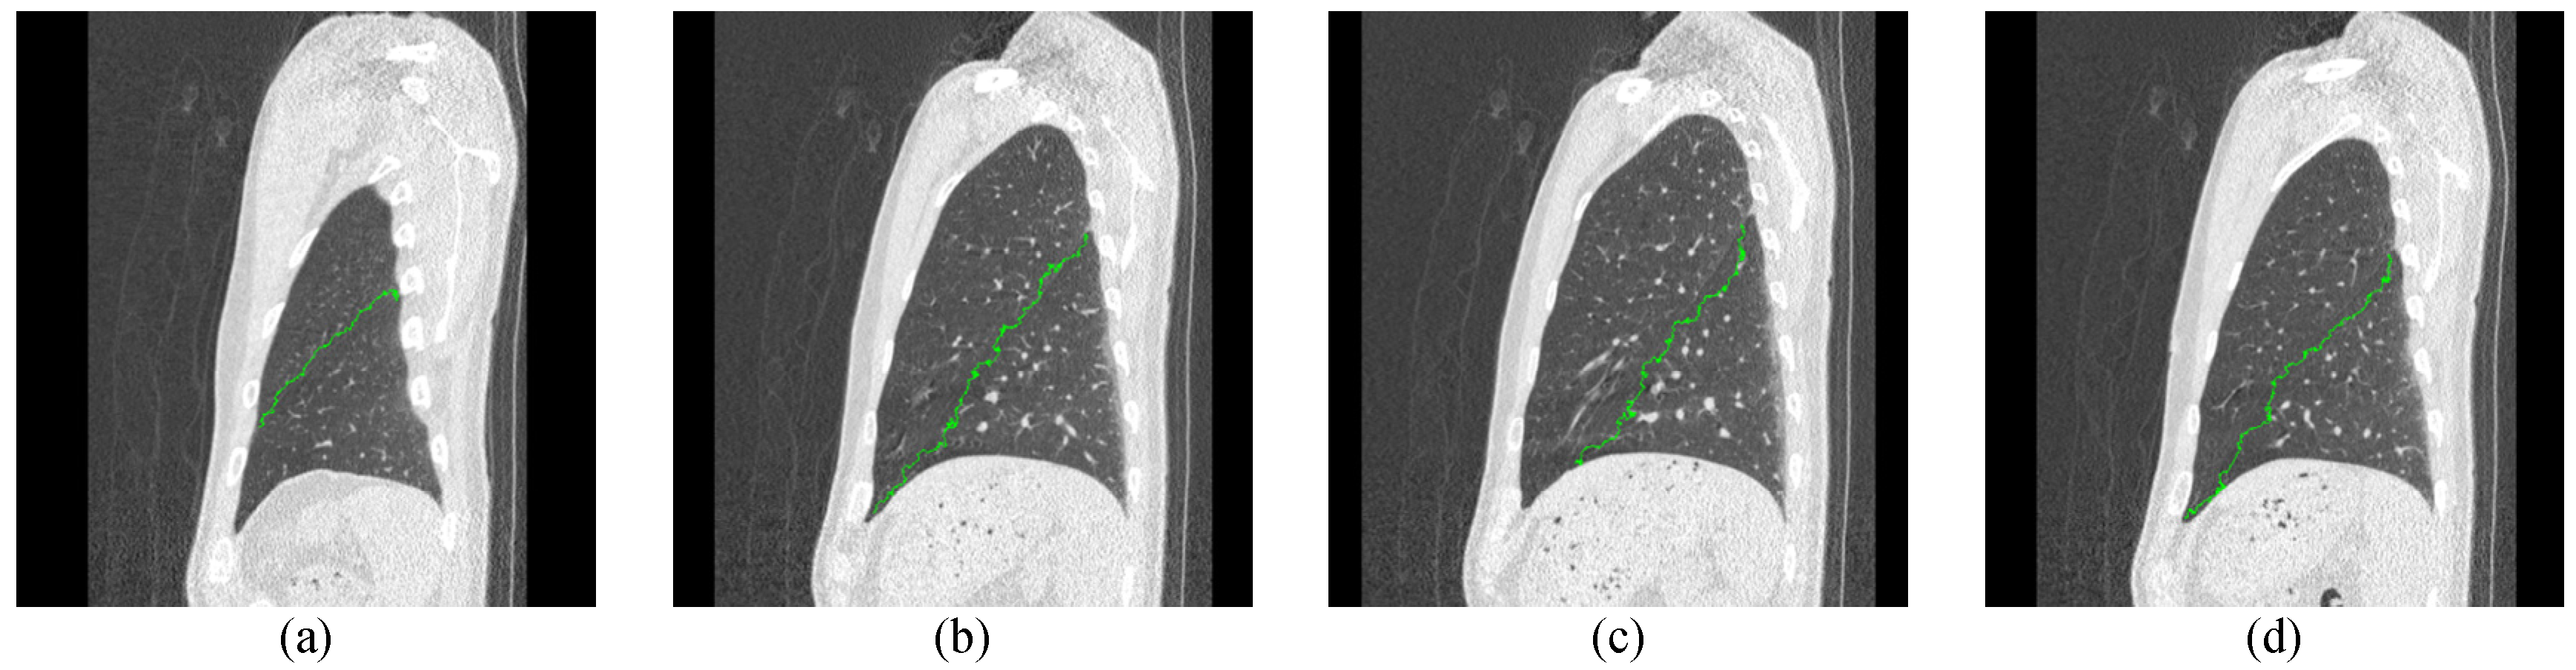

4. Experimental Results